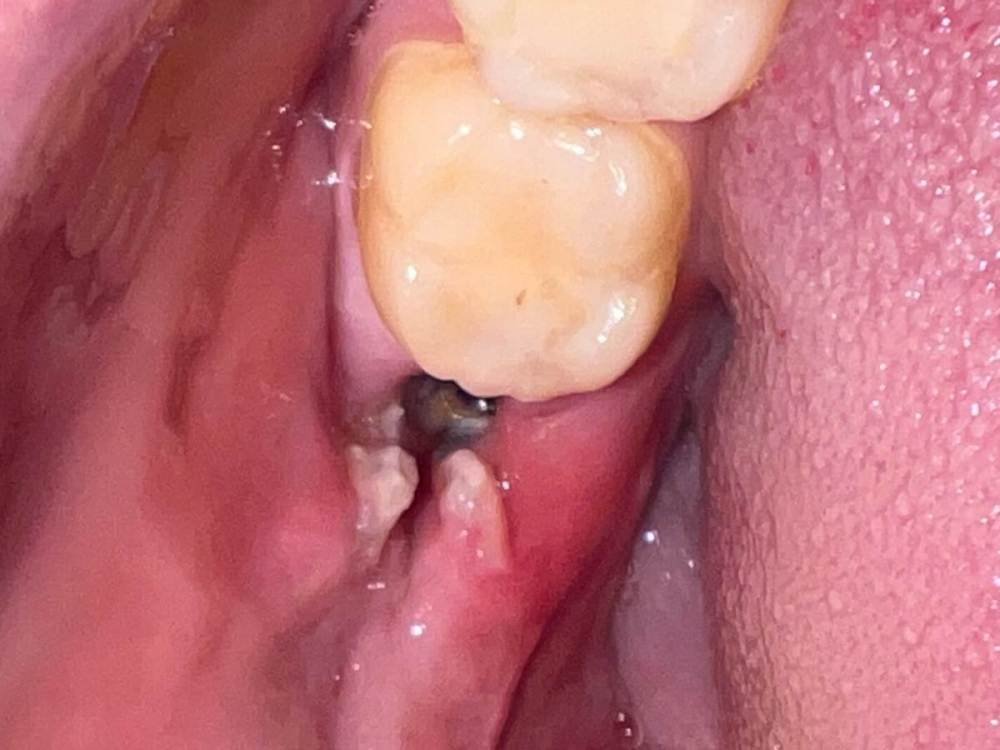

JeanneK Опубликовано 12 июля, 2023 Поделиться Опубликовано 12 июля, 2023 Добрый день. Сегодня третий день после удаления нижней восьмерки, ничего не резали, просто расшатали и вынули. Был довольно крупный капюшон над зубом. Сегодня все это выглядит вот так, крупного кровяного сгустка не было, первый день кровило. Рекомендации врача соблюдала, ничего не выплевывала и не видела, чтобы сгусток выпадал. Гемостатическую губку я не заметила, чтобы ставили. Сейчас не кровит, отека почти нет, но десна умеренно ноет, неприятного запаха нет. 1. Затянется ли дыра, это не сухая лунка? 2. После еды можно ли (нужно ли) держать немного хлоргексидина/мирамистина/метрогил-денты, чтобы обеззаразить? ? Спасибо Ссылка на комментарий

JeanneK Опубликовано 12 июля, 2023 Автор Поделиться Опубликовано 12 июля, 2023 Еще на фото видно красную воспаленную десну, там прям болит. К вечеру сильно разболелось... идти завтра к врачу или все в рамках нормы? Ссылка на комментарий